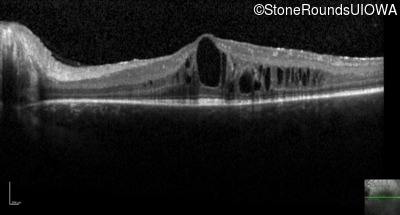

Optical Coherence Tomography - Right - 20/30 -1

Exemplar / OCT Stack

OCT Stack